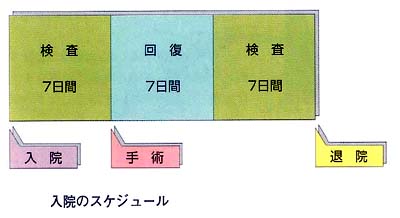

入院のスケジュール

脳下垂体腫瘍の手術治療を目的とする場合、入院期間はおよそ3週間です。

手術前には、1週間をかけて先に述べた様々な検査を行ないます。但し、事前の内分泌的な検査が不十分な場合は10日間程かかることもあります。また、看護師の側から、特に経鼻手術に関しては特別な注意や訓練が行なわれます。例えば、うがいの励行や鼻腔内のパックの練習等です。

手術後は、手術の内容や個人差にもよりますが、早い人では翌日から、遅くとも4〜5日目頃から歩行可能となります。手術後1週間くらいは、様々な注射があったり、手術自体の影響が残っていますが、2週間目にはこれらもほとんどなくなります。そこで手術後のホルモン検査(手術前のそれを若干簡便にしたもの)を行ないます。

以上より、全て順調に運べば手術後14日前後で退院出来るわけです。